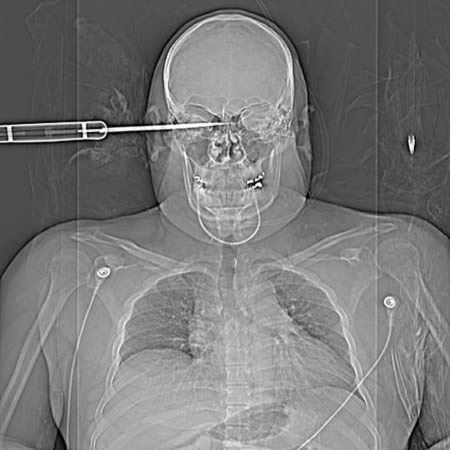

23-летний мужчина выжил после того, как ему проткнули левую глазницу мечом. Буй Нгок Туан получил удар 50-сантиметровым мечом от водителя такси. Меч проник почти на 10 сантиметров вглубь.